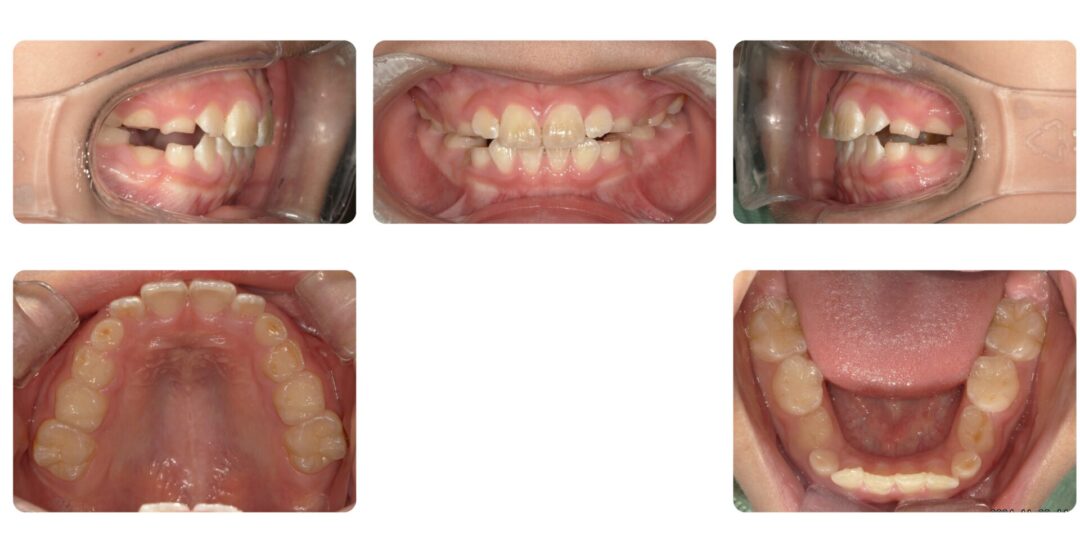

過蓋咬合を伴うアングル2級咬合|初診時7歳

矯正治療後

治療内容

第一期治療 拡大床ネジ付きバイトプレートによる歯列矯正

治療期間

1年7ヶ月